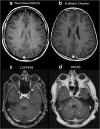

Purpose: Miliary enhancement refers to the presence of multiple small, monomorphic, enhancing foci on T1-weighted post-contrast MRI images. In the absence of a clear clinical presentation, a broad differential diagnosis may result in invasive procedures and possibly brain biopsy for diagnostic purposes.

Methods: An extensive review of the literature is provided for diseases that may present with miliary enhancement on T1-weighted brain MR images. Additional disease-specific findings, both clinical and radiological, are summarized and categorized by the presence or absence of perivascular space involvement.

Results: Miliary pattern of enhancement may be due to a variety of underlying causes, including inflammatory, infectious, nutritional or neoplastic processes. The recognition of disease spread along the perivascular spaces in addition to the detection or exclusion of disease-specific features on MRI images, such as leptomeningeal enhancement, presence of haemorrhagic lesions, spinal cord involvement and specific localisation or systemic involvement, allows to narrow the potential differential diagnoses.